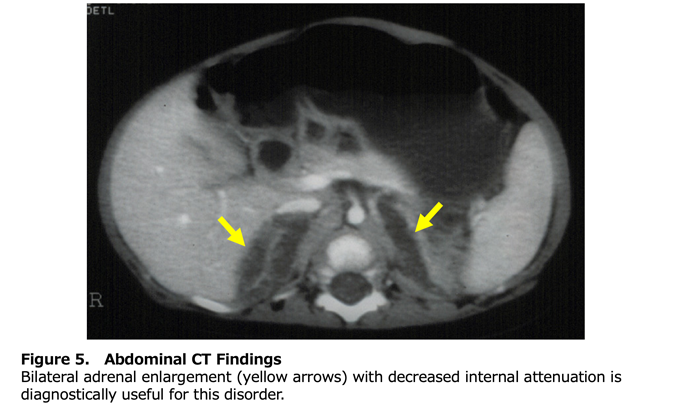

Table 2 presents the diagnostic criteria for this designated intractable disease. Classical LCAH should be suspected when all adrenal and gonadal steroid hormones are low, plasma ACTH, plasma renin, and serum gonadotropins are all elevated, and external genitalia are completely female in appearance. As with other forms of primary adrenocortical insufficiency, routine laboratory studies should assess for hyponatremia, hyperkalemia, and hypoglycemia. Abdominal computed tomography (CT) is the most informative imaging modality. Enlarged adrenal glands with decreased CT attenuation due to lipid accumulation (fatty attenuation) are seen in 86% of classical cases and are specific to LCAH (Figure 5) (7). However, the absence of adrenal enlargement does not exclude the diagnosis. In 46,XY individuals, ultrasound can identify testes along the path from the scrotum or labioscrotal folds through the inguinal canal. Genetic analysis of the STAR gene is highly valuable for diagnosis. It is particularly important for distinguishing LCAH from cholesterol side-chain cleavage enzyme deficiency when adrenal enlargement is absent, and for differentiating classical or non-classical LCAH from ACTH unresponsiveness in 46,XX individuals with preserved ovarian function or in 46,XY non-classical cases with preserved testicular function.